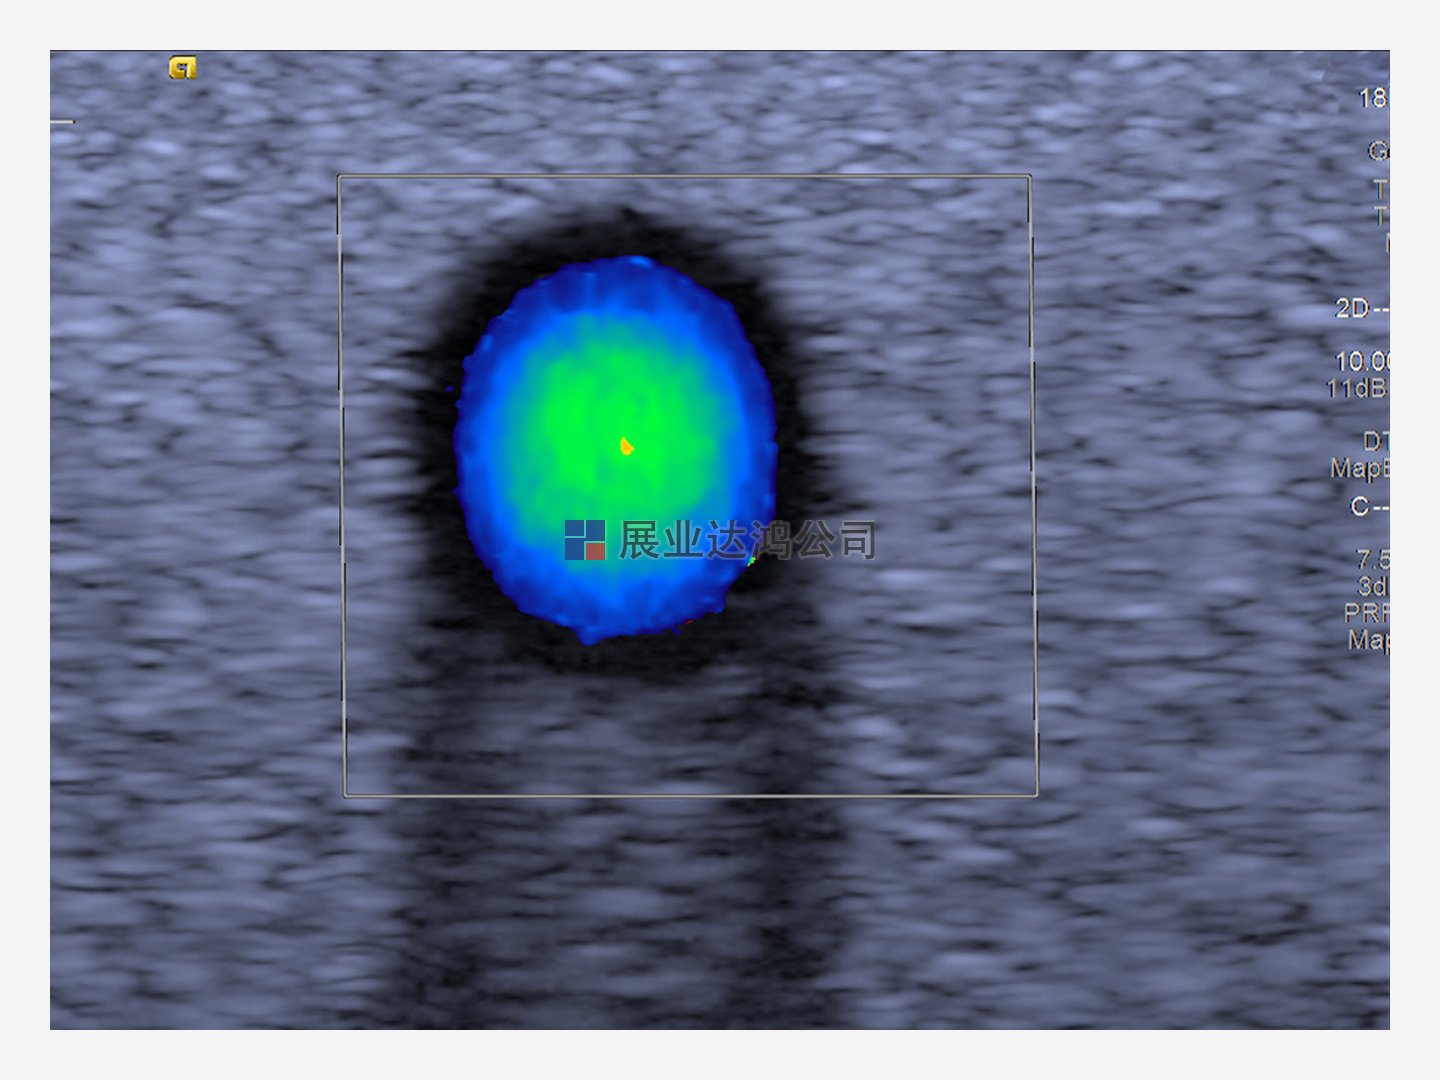

橫截面圖像顯示了管道中心的最高速度,代表了層流拋物線流的測量

可用的層流和拋物線流(取決于速度)